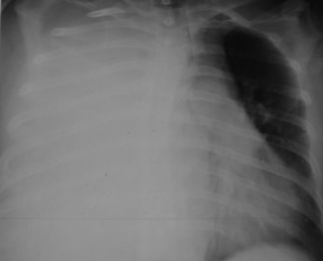

DESCRIERE:

la nivelul hemitoracelui stg → hipertransparență fără desen vascular pulmonar, cu colabarea plămânului spre hil (aspect de opacitate ca un “bont“)

diafragm deplasat în jos

lărgirea spațiilor intercostale

DX: pneumotorax total

DD:

emfizem pulmonar - desen vascular păstrat

bulă gigantică de emfizem - nu se văd pleura viscerală și plămânul colabat

agenezie congenitală de parenchim pulmonar